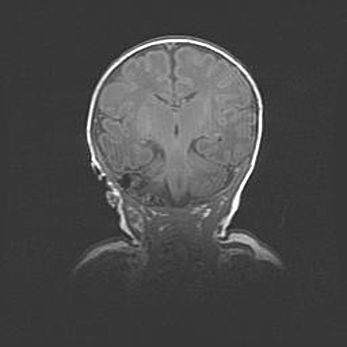

Подострая гематома правой гемисферы мозжечка.

Наружная гидроцефалия.

Возраст: 15 дней

Вес: 3100 г

Пол: женский

Окружность головы: 37 см

Срок гестации: 35-36 недель

При открытой наружной форме гидроцефалии у новорожденных расширяются и переполняются субарахноидные пространства.

Кровоизлияния в мозжечок имеют две клинико-анатомические формы: полушарные гематомы и кровоизлияния в червь.

К появлению этой патологии может привести: повреждения головного мозга, возникающие в результате асфиксии и гипоксии плода при беременности, или травмы во время родов. Редко гематома мозжечка может быть результатом первичной коагулопатии и сосудистой мальформации, диссеминированном внутрисосудистом свертывании, изоиммунной тромбоцитопении.